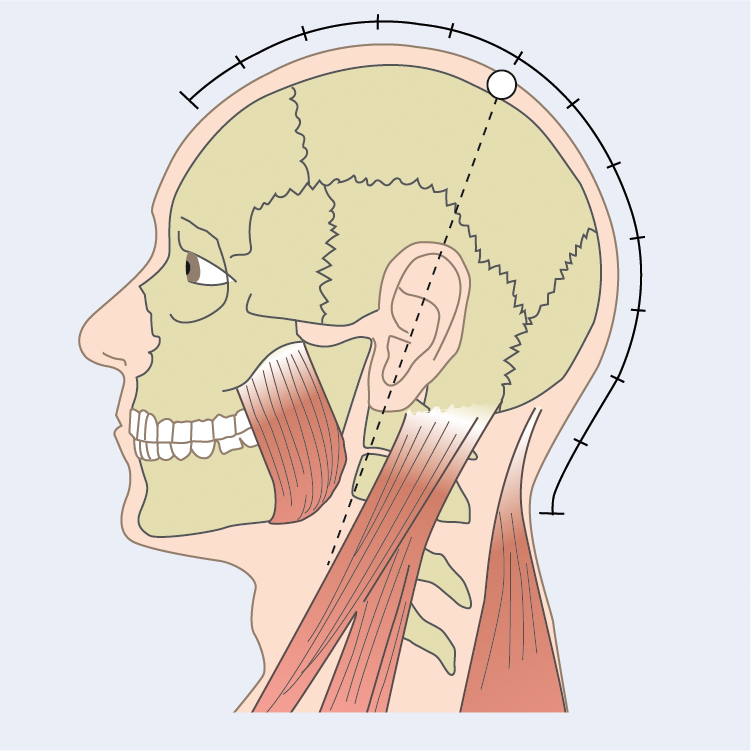

Medizinische Zeichnungen und Kinderbuch Illustration

Herzlich willkommen! Ich bin Ihre Expertin für medizinische Illustrationen und kreative Kinderbuch-Illustrationen. Mit einem Auge für wissenschaftliche Genauigkeit und einer Liebe zur Gestaltung kindgerechter Erzählwelten schaffe ich Bilder, die informieren und begeistern. Entdecken Sie mein Portfolio und lassen Sie sich von meiner Arbeit überzeugen!